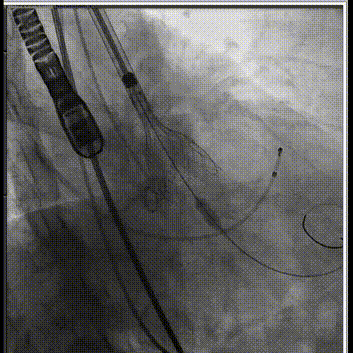

主动脉根部造影

球囊预扩

释放工作位评估

术后造影评估

人工瓣膜精准定位